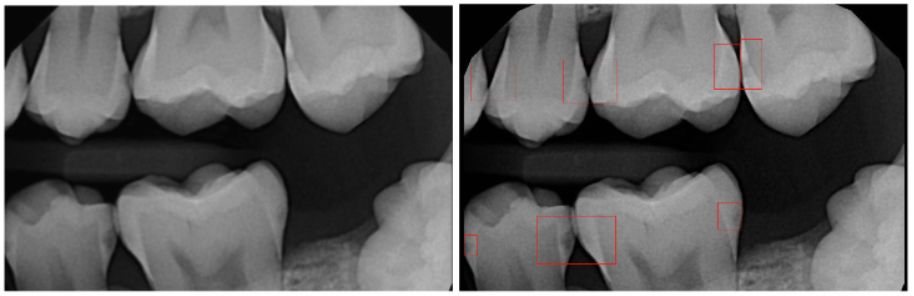

口腔医疗领域盛产大量的牙科X光检查图像数据,容易匿名化,在开发牙科的AI放射训练系统时非常有价值,方便AI技术的介入。并且对于牙医来说,没有像其他内科、专科医生一样可以配备训练有素的放射科技师,口腔AI的影像分析可以作为媲美人类的准确率较高的助手来使用,成为牙医的第二双火眼金睛。

在口腔医疗领域,AI应用最为广泛的也是跟阅片检测相关。拿患病率最高的龋齿来说,传统的诊断依靠X 射线牙片及直接的口内检查,以此发现咬合龋。但对于牙齿根部的龋齿、临间龋和根面龋等潜在龋齿,难以发现,容易漏诊。辅助龋齿检测的AI模型可以代替医生对牙片进行精准的龋齿侦查,这种专项的AI模型对龋齿斑的敏感度高于人类有限的视力。

当然,除了局部专项的阅片外,在整体口腔问题识别上面,AI也有所作为。

牙医上传牙齿全景片后,AI系统可以识别出全景片中的关键结构和患者可能存在的几十项口腔问题,并自动为患者生成一份精细的个性化口腔健康报告。与此同时,对于牙齿疾病的未来发展,也可以通过数字化建模推演未来疾病的发展趋势,患者可以直观和深入了解自身的口腔问题,提升就诊率和流失率。